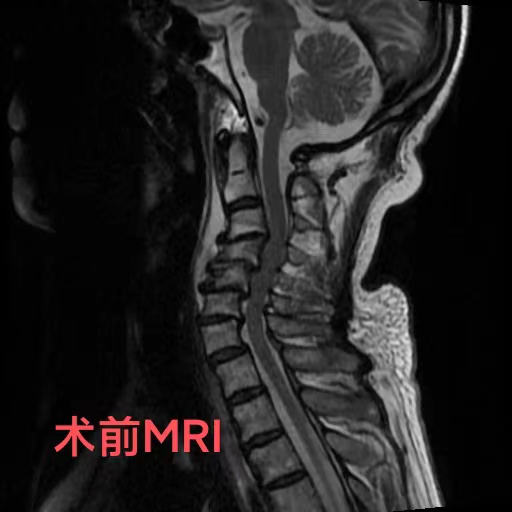

“这么严重的颈椎变形,少见啊!”什么样的颈椎现状让见识广阔的康复医学科医生都不禁发出如此感叹?